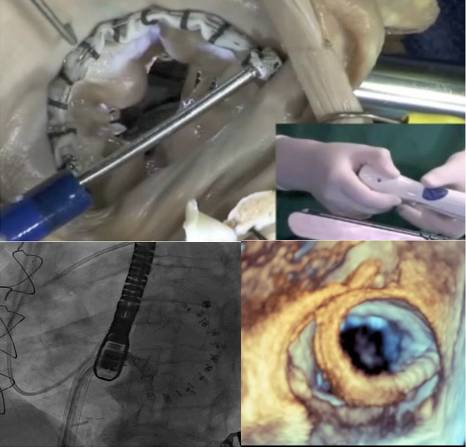

治疗MR的其他方法

[9]

◆Functional MR

—Coronary sinus annular devices

—Direct annuloplasty

—Septal shortening devices

◆Degenerative MR

—Percutaneous neochords

◆Both

—TMVR

Direct Annuloplasty Approaches

Cordal Approaches

Transapical Neochord Repair

[11]

Trans-catheter Mitral Valve Replacement TMVR

◆TS and TA access approaches

◆All self expanding

◆All in the FIM or Phase 1 trials

Acute Human Use, February 2013

[12]